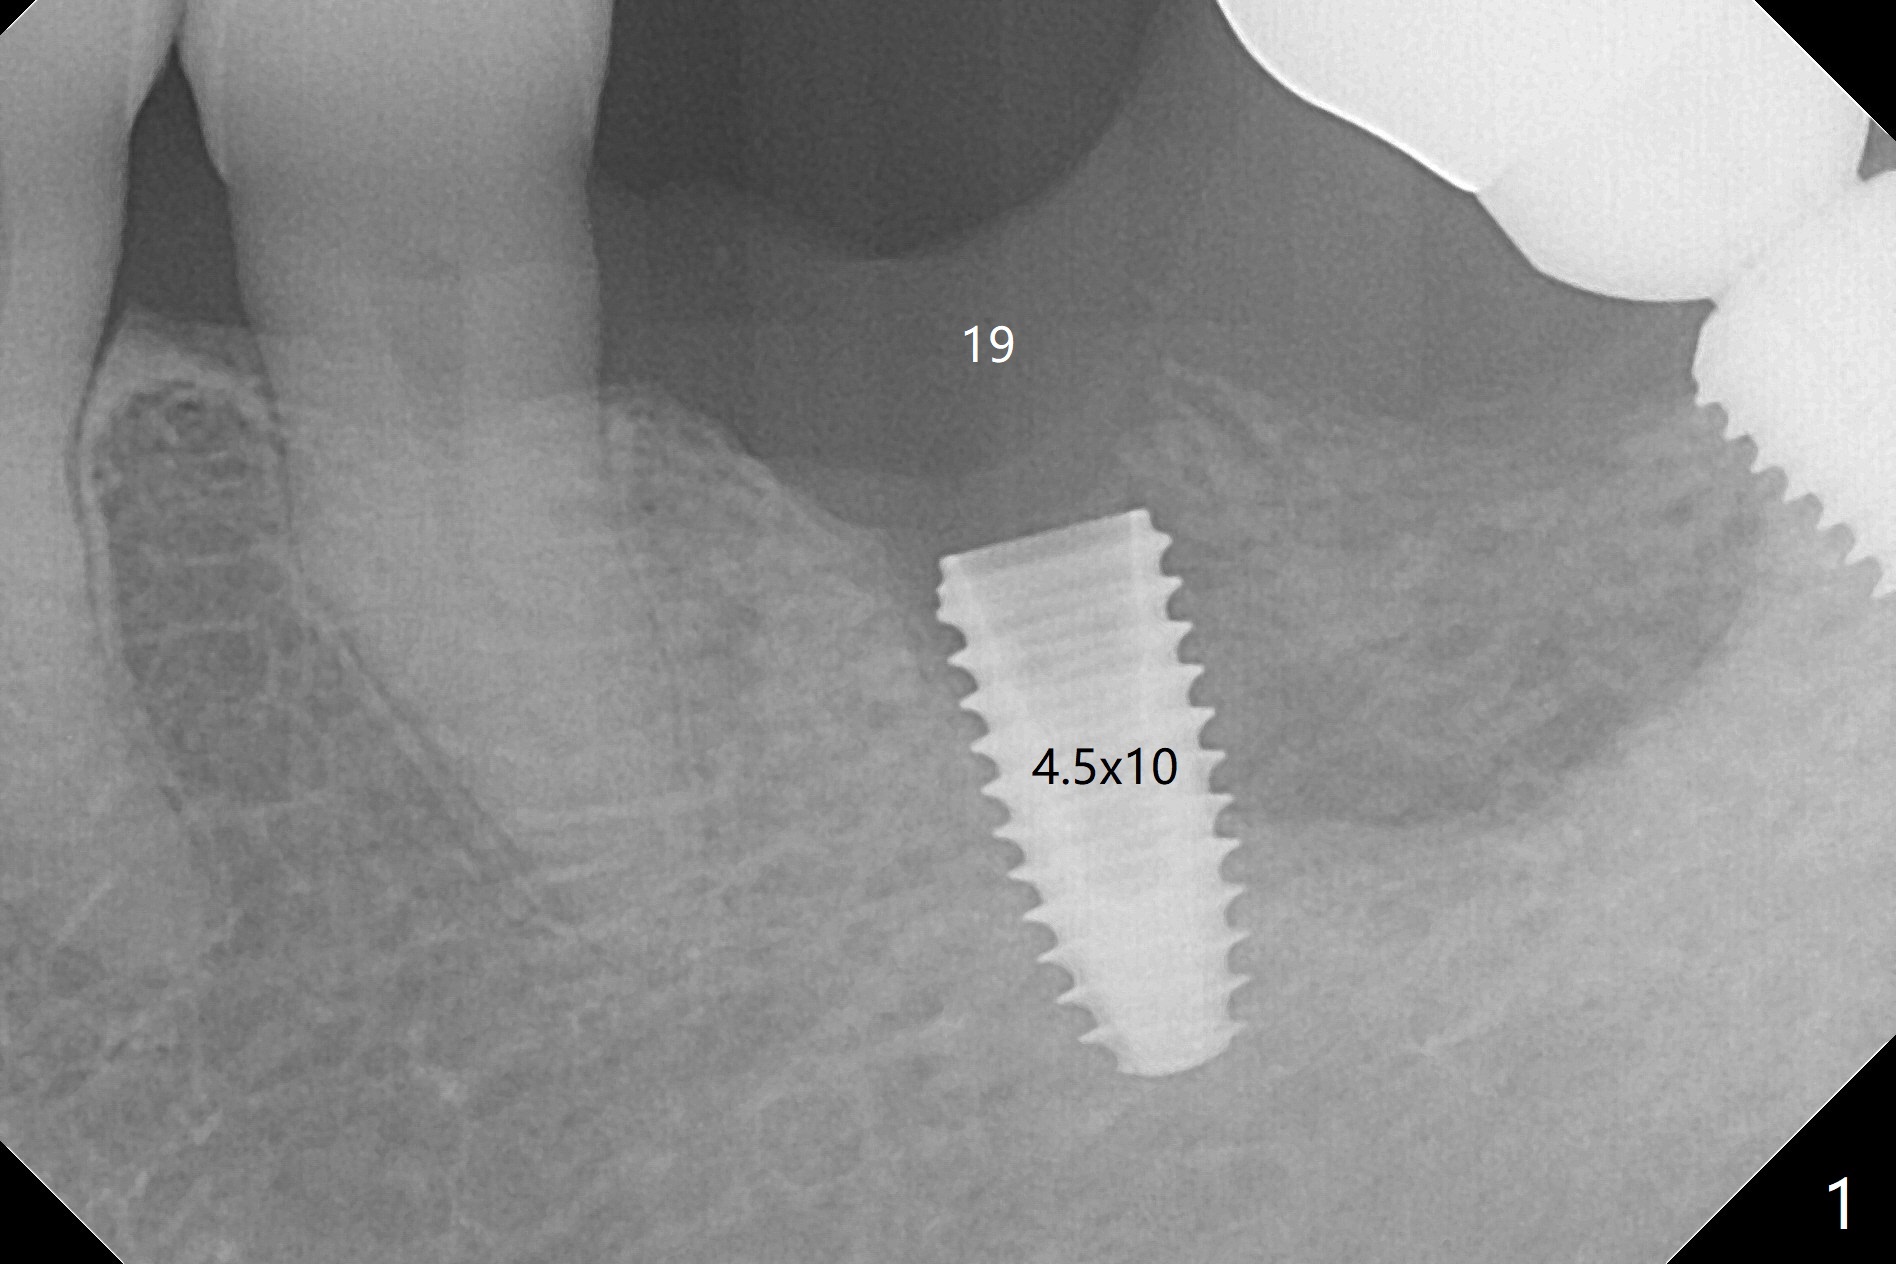

Probably due to severe infection at #19, pain control is difficult. Osteotomy has to be stopped 1.5 mm short of the design. PA taken with a 4.5x10 mm dummy implant does not show the Inferior Alveolar Canal (Fig.1), whereas CT does (Fig.2). With 6 mm clearance, block anesthesia is administered. A 5x10 mm definitive implant is placed with ease (Fig.3). The buccal bony defect is repaired by allograft (Fig.3,4 *), while the soft one by 3 pieces of PRF membrane (Fig.5). The latter is fixed in place by applying setting acrylic as an immediate provisional (Fig.6 P) over the wound, around the abutment (A) and locking into the undercut of the neighboring tooth/implant crown. The patient feels great postop. The gingiva is healthy around the provisional 8 days postop (Fig.7). The patient remains asymptomatic with the healthier gingiva surrounding the simplified provisional 22 days postop, as compared to 8 days postop (Fig.8). The socket heals when the simplified provisional is removed 1.5 months postop (Fig.9-12). The bone graft (Fig.11 ^) seems to have become a part of the regenerated gingiva. The abutment has been dislodged for 2 week (Fig.14 (3 months postop). The bone graft, albeit decreased, is 2 mm subgingival (red dashed line). There is bone distal to the implant 11 months postop (Fig.15 *). There is no bone loss 2 years postop; the UF abutment is completely seated (Fig.16).